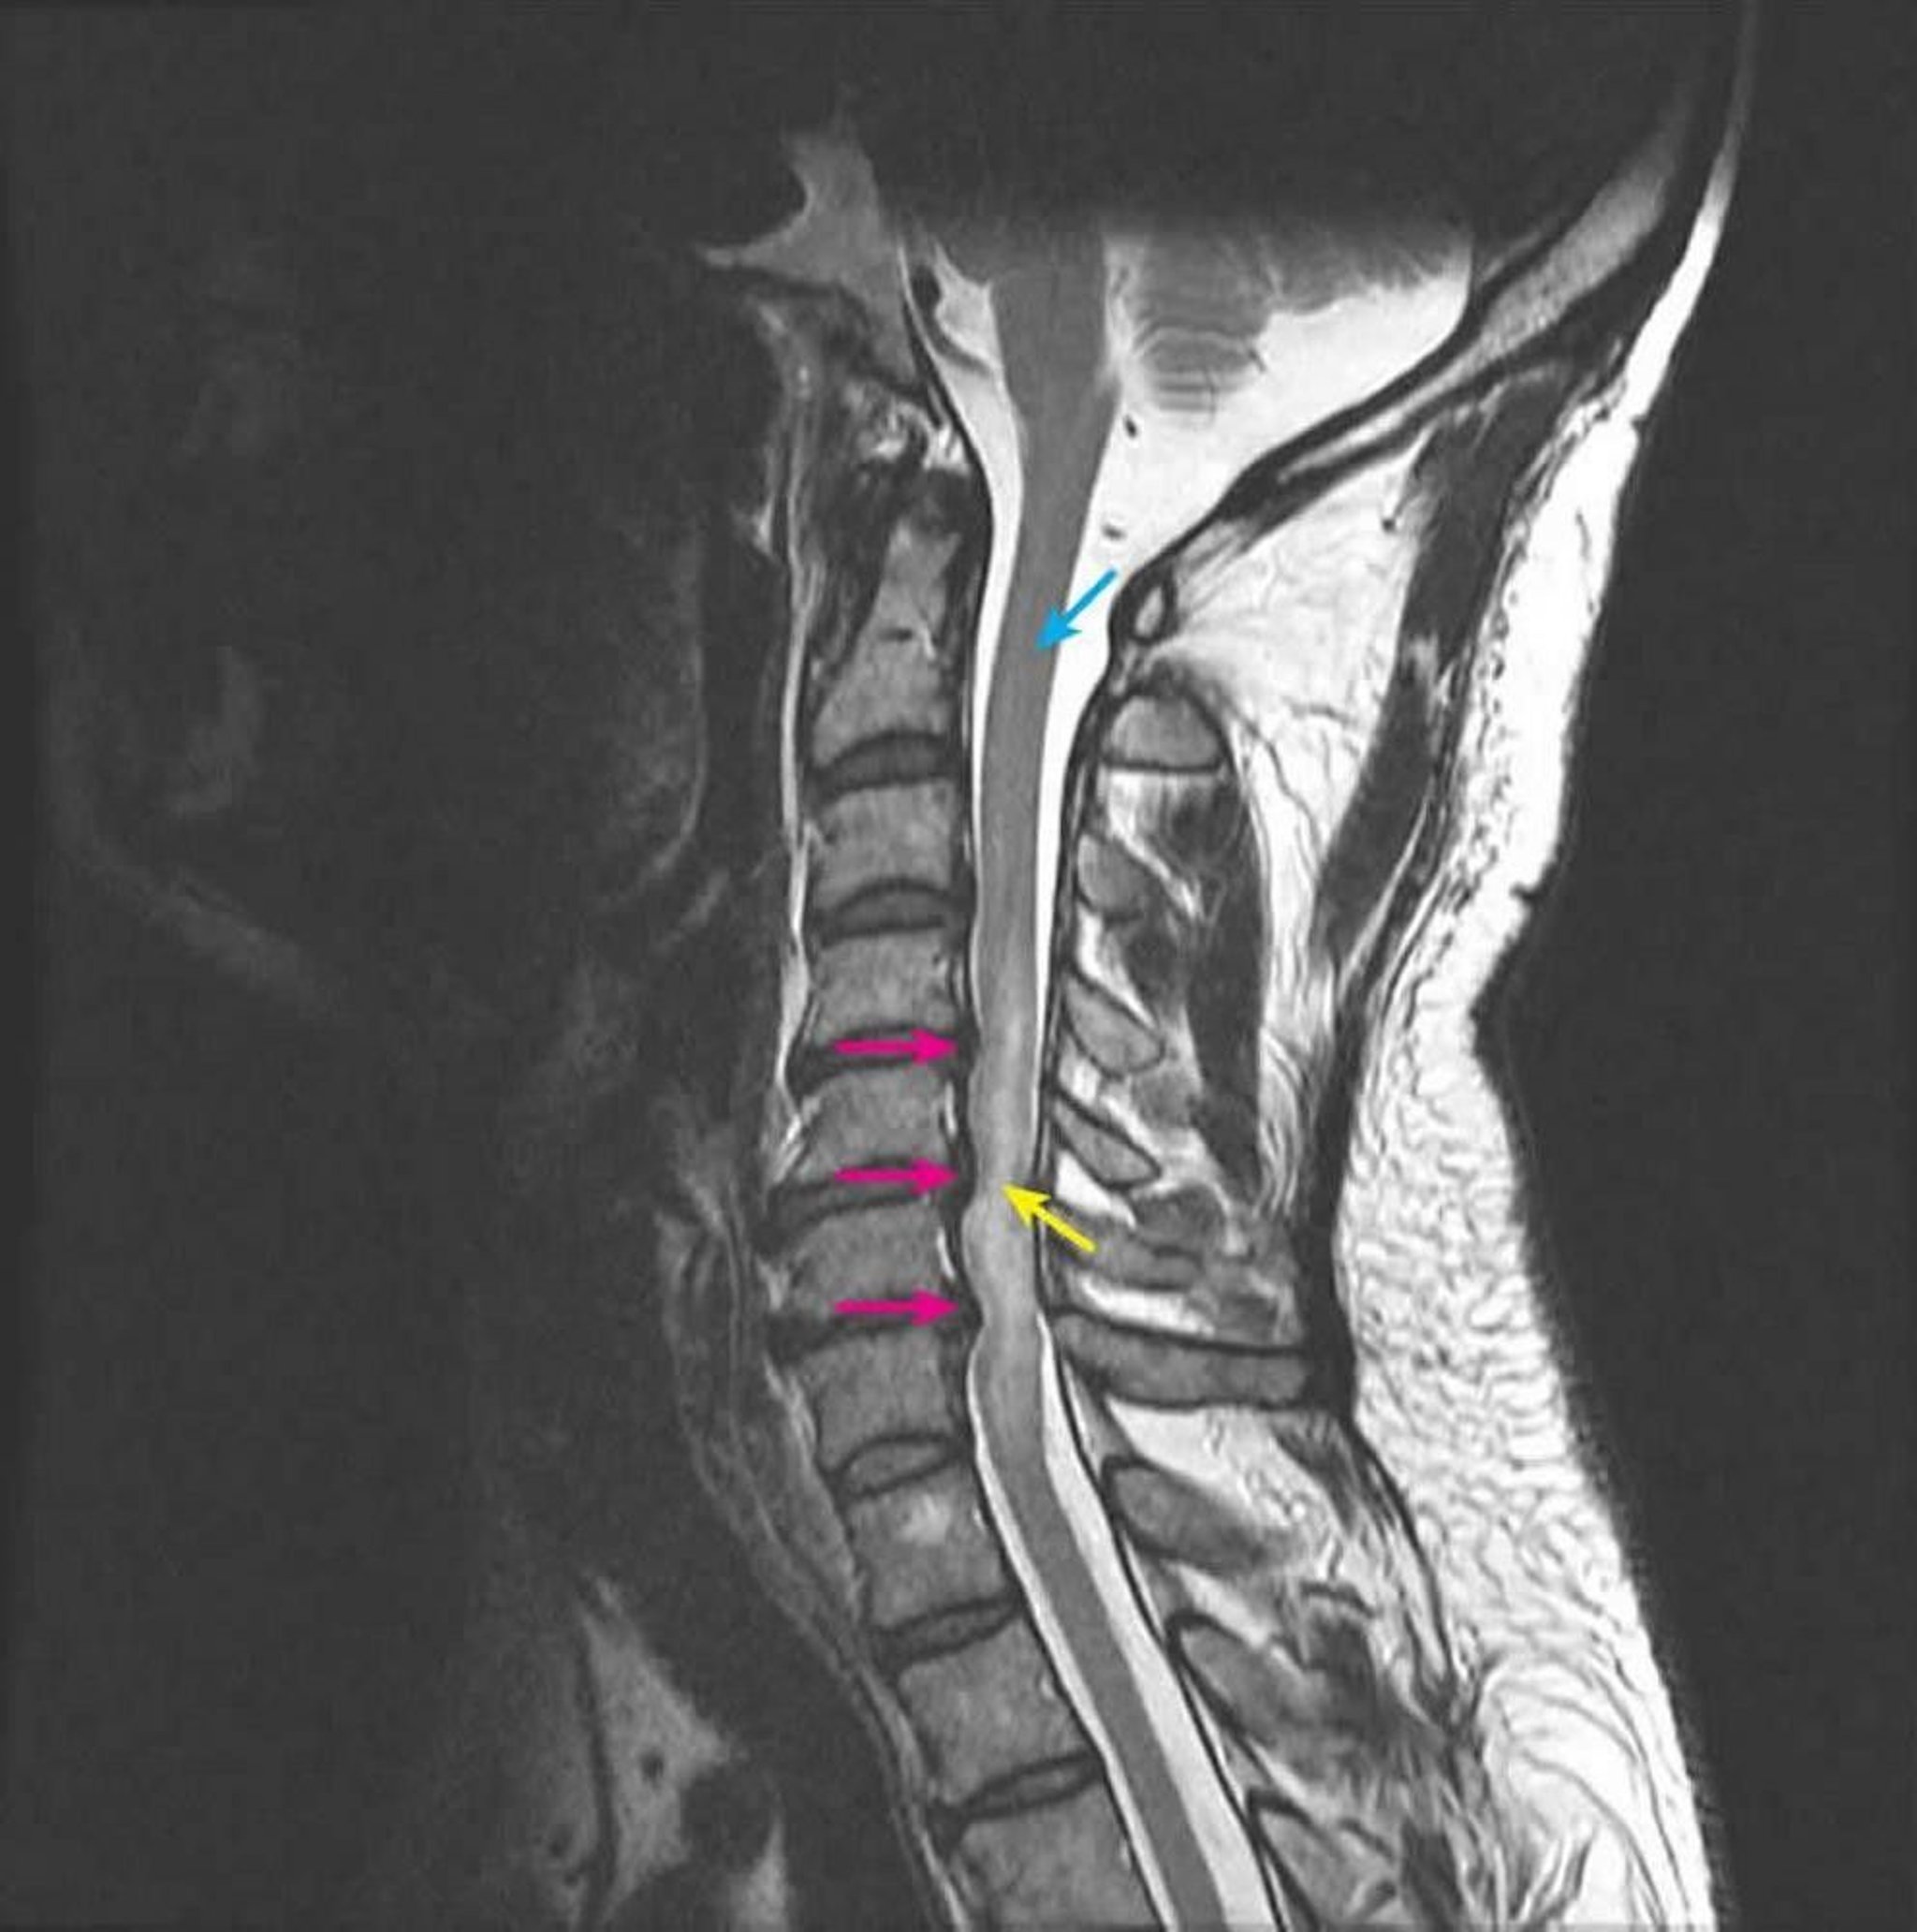

Compressive Myelopathy

Sagittal T2-weighted MRI shows spinal cord compression at the C4-5, C5-6, and C6-7 intervertebral levels secondary to multilevel posterior disc herniations (pink arrows). The intramedullary T2 signal is abnormally increased, representing spinal cord edema (yellow arrow). The normal spinal cord signal is seen at the C2 level (blue arrow).

Courtesy of John Tsiouris, MD, Division of Neuroradiology, New York–Presbyterian Hospital/Weill Cornell Medical Center.